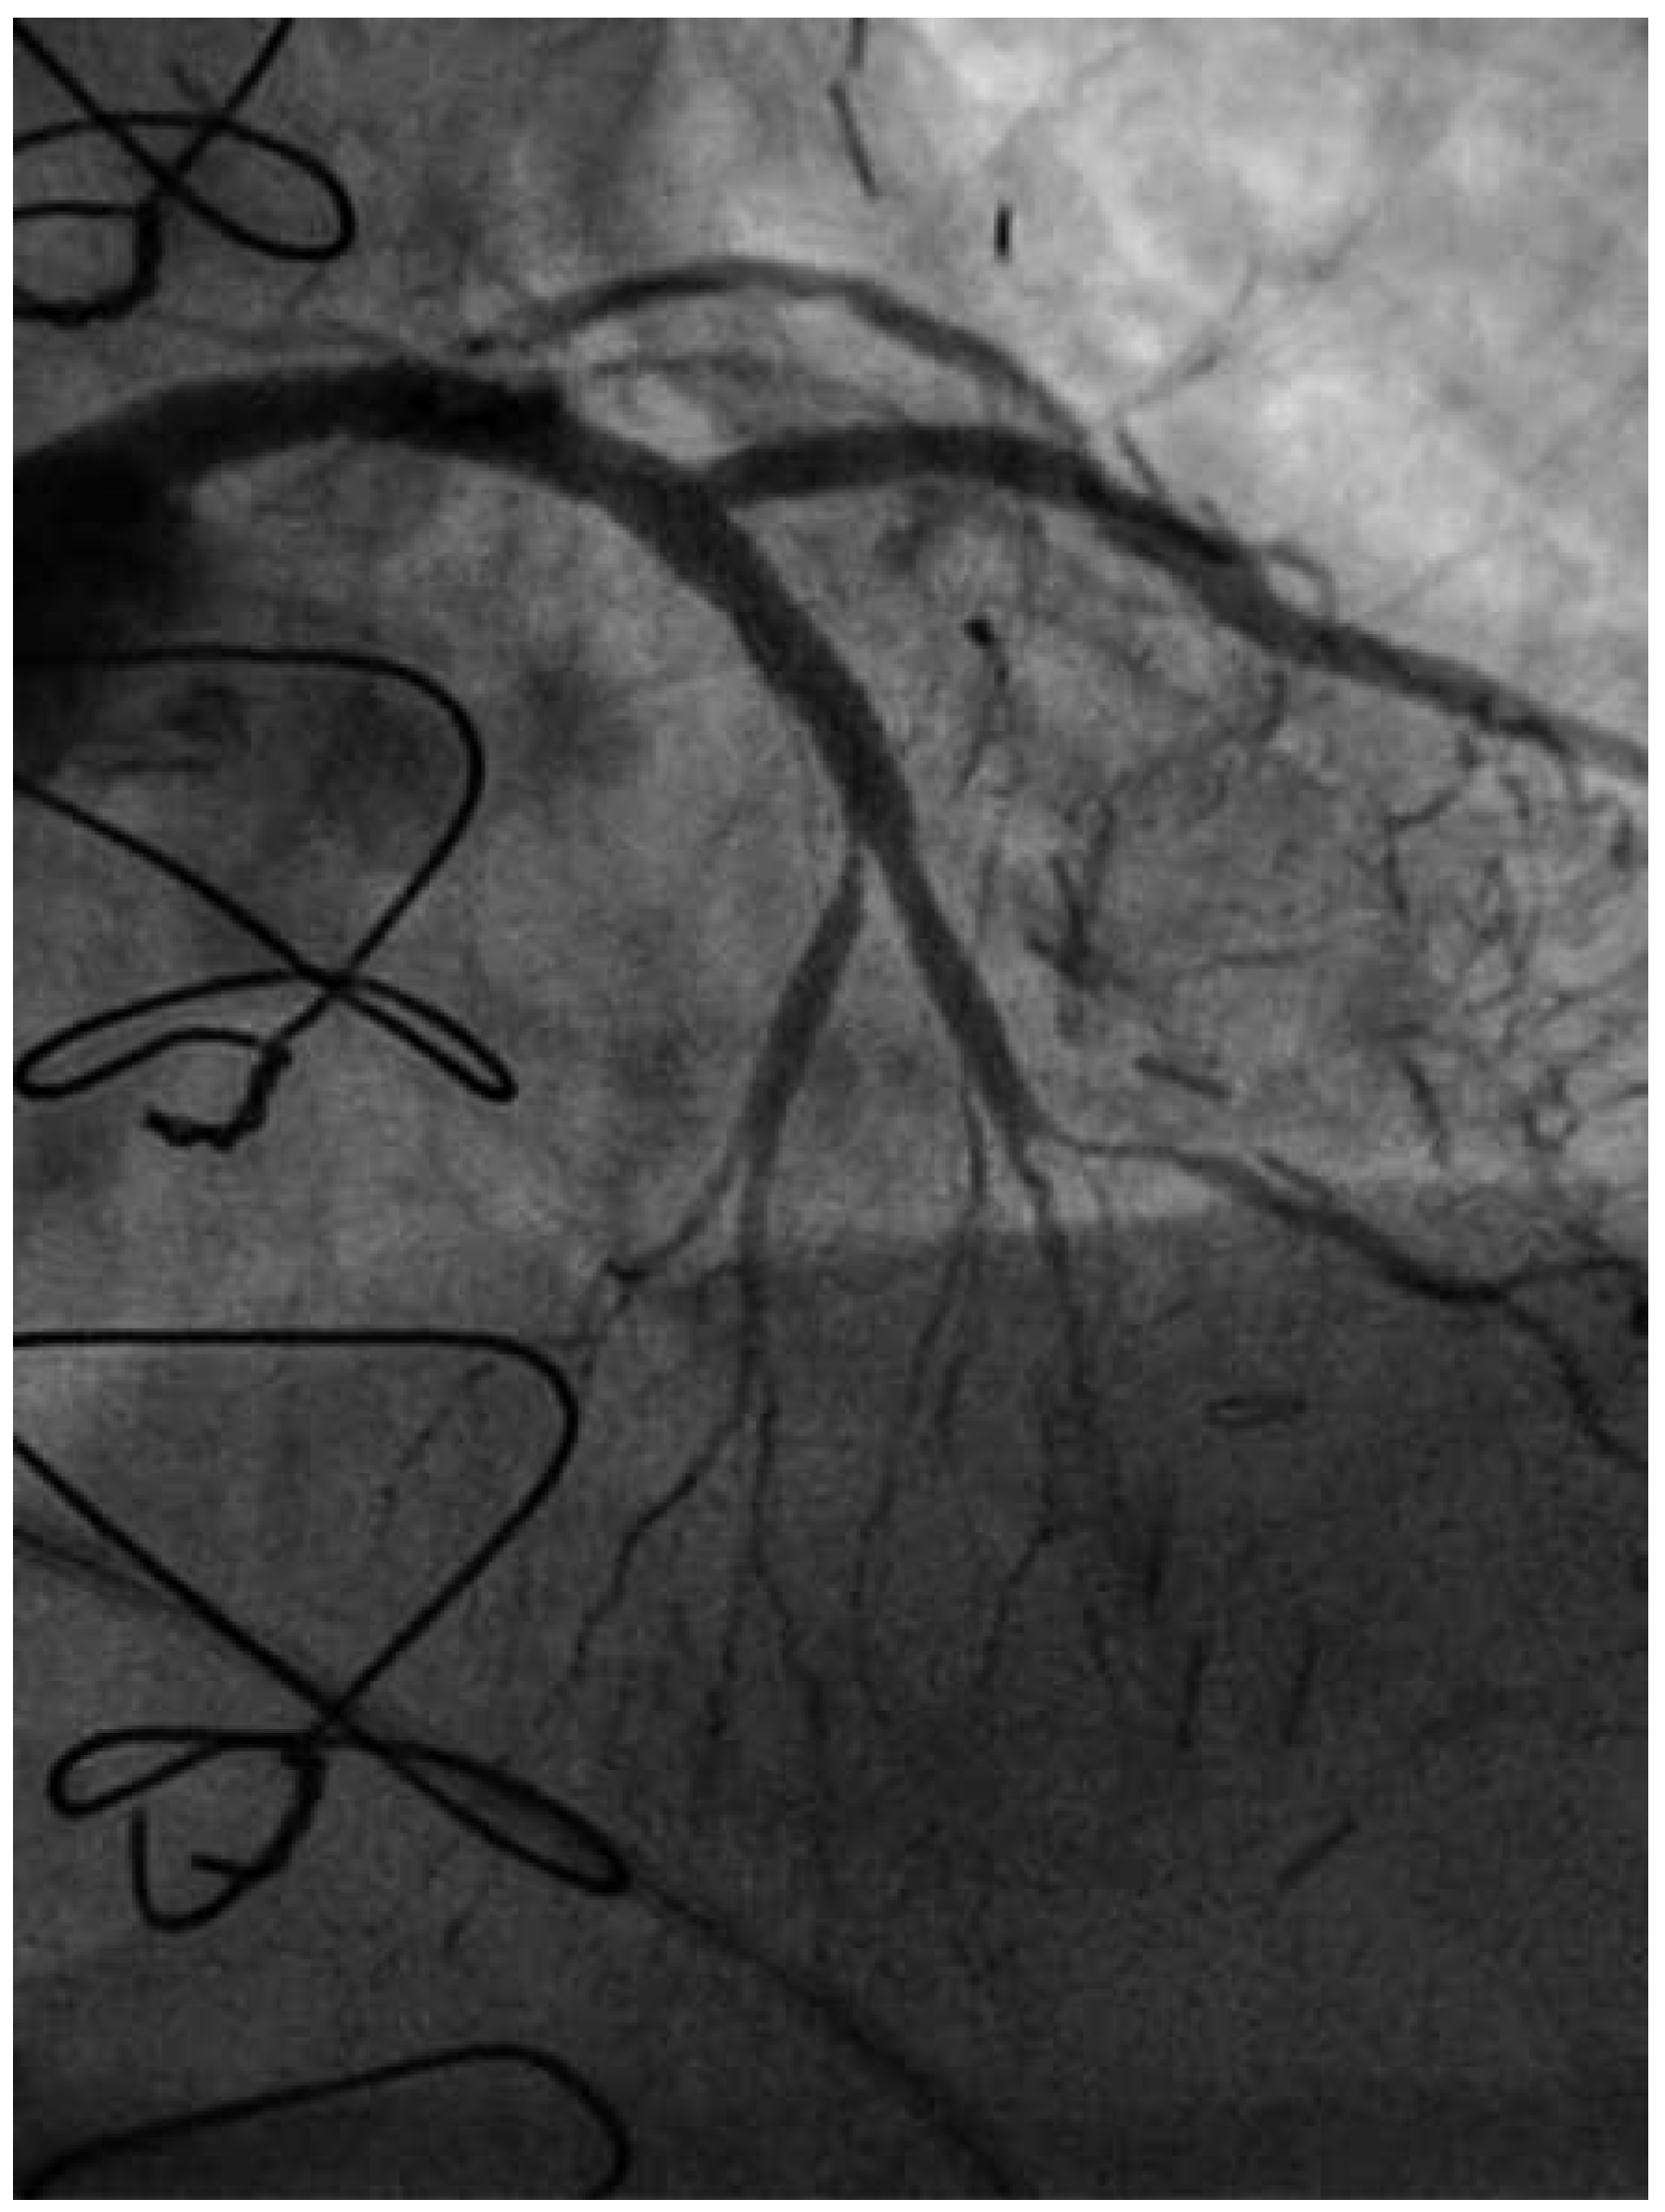

Coronary angiography of the left coronary system demonstrated severe left main stem (LMS) disease (Figure 1). The severe LAD in-stent restenosis was very eccentric and appeared to be restricting the origin of a sizeable diagonal branch, which also had severe disease. Distally, the LAD was occluded at the point where another stent had been inserted previously and just beyond a large septal perforator. The Cx had severe ostial disease and gave rise to a heavily diseased first obtuse marginal branch. The remainder of Cx and right coronary artery (RCA) systems were occluded proximally, with absent collaterals. The only patent graft was the LIMA, anastomosed very distally to the LAD (Figure 2). Following discussion, it was felt that neither Cx nor RCA were suitable targets for surgery and we therefore undertook intervention to the LMS and LAD / first diagonal bifurcation.

Figure 1. RAO 15°, cranial 40° view. of the left coronary system. Note the diseased LMS (A), the proximal LAD stent at the diagonal bifurcation (B) and the distal LAD stent (C).